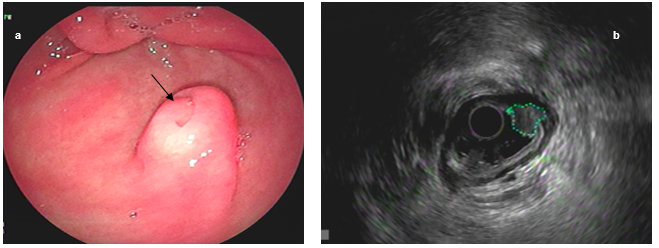

23 patients were included, of which 15 were women (65%) and 8 men (35%), the average age was 47 years (range 8-69 years). Table 1. Regarding the lesions, 19 (19/23, 82%) were located in the antrum, 1 (1/23, 4%) in the body antral junction and 3 (3/23, 13%) in the duodenal bulb. Central umbilication was identified in 21 of the cases (91%). Figure 1.

Figure 1. Antral ectopic pancreas with (a) central umbilication (arrow). Endosonographic appearance (b), delimited lesion (dotted line)